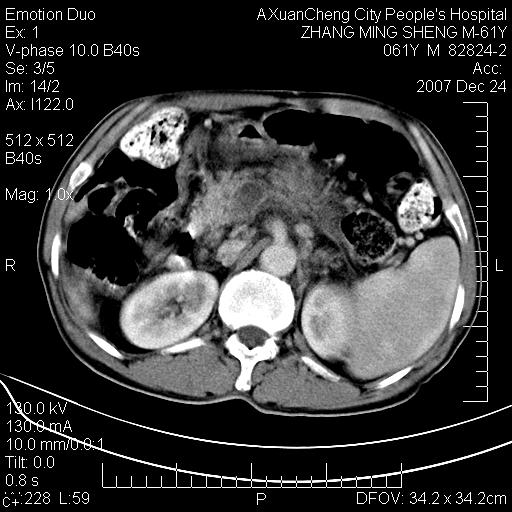

标题: CT11031:M61Y,胰腺占位

大家侃侃门静脉和胆管系统怎么回事,肝内转移?

胰腺癌肝转移

肝硬化,门脉高压,脾肿大;弥漫性肝癌,肝内、门脉、腹膜后淋巴结转移,肝内外胆管扩张,胰头区占位,建议mr检查

胰腺癌伴肝内转移;门脉、肠系膜上v癌栓形成。

考虑为:胰腺癌伴肝脏转移、腹膜后淋巴结转移,门静脉及肠系膜上静脉瘤栓形成。

胰体尾癌伴肝内转移,门静脉及肠系膜上静脉瘤栓形成.